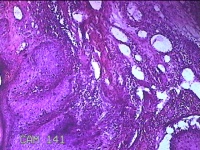

额部肿物

性别

女

年龄

32岁

临床诊断

寻常疣

一般病史

额部起疹1年,不痒。

标本名称

大体所见

灰白暗红色肿物0.7x0.5x0.2cm一个,表面光滑,切开肿物呈实性,切面灰白粉红色,质软。

图1